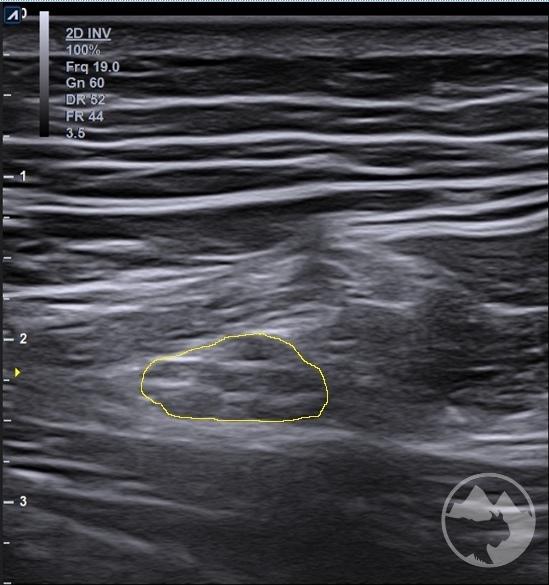

Workshop bude zaměřen nejen na samotné zobrazení daných nervů ve svém průběhu, nýbrž i na důležité topografické souvislosti s dalšími strukturami jako jsou kosti, svaly, cévy, vazy nebo fascie a na identifikaci anatomických „markerů“ a rizikových míst. V rámci několika přednášek budou zopakovány anatomické průběhy nejčastěji vyšetřovaných nervů včetně běžných variací, budou prezentovány možnosti měření, správného nastavení dopplerovského módu, ukázky úžinových syndromů a jiných patologických nálezů včetně důležitých „redflags“. Převažovat však budou praktické ukázky vyšetření a nácviky v malých skupinách. Vyšetřovací postupy zahrnou běžné statické zobrazení i skenování při pohybu, tzn. testy neurodynamiky. K dispozici na vyzkoušení budou standardní sondy i moderní vysokofrekvenční sondy s rozlišením umožňujícím hodnocení jednotlivých nervových fasciklů. Součástí přednášek ani praktických nácviků nebudou intervenční postupy.